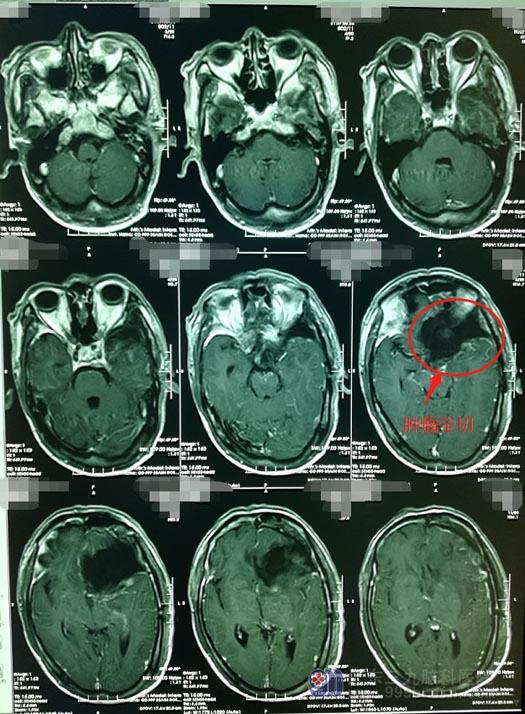

▲术后MR

术后仅半天时间,各项指标均显示石先生已无大碍,遂转入普通病房,目前一切恢复正常。